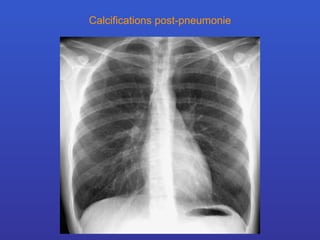

Calcifications post-pneumonie

Calcifications pulmonaires Analyse en fonction de leur aspect morphologique calcification diffuses d’aspect miliaire -  histoplasmose, hémosidérose, tbc calcifications nodulaires multiples -  parasitoses, silicose, varicelle ossifications de forme nodulaire -  calcifications valvulaires mitrale calcification nodulaire unique -  tuberculose, hématome calcifications au sein de nodules multiples - métastases chondrosarcome, ostéosarcome calcifications arciformes -  paroi d’une bulle, kyste hydatique